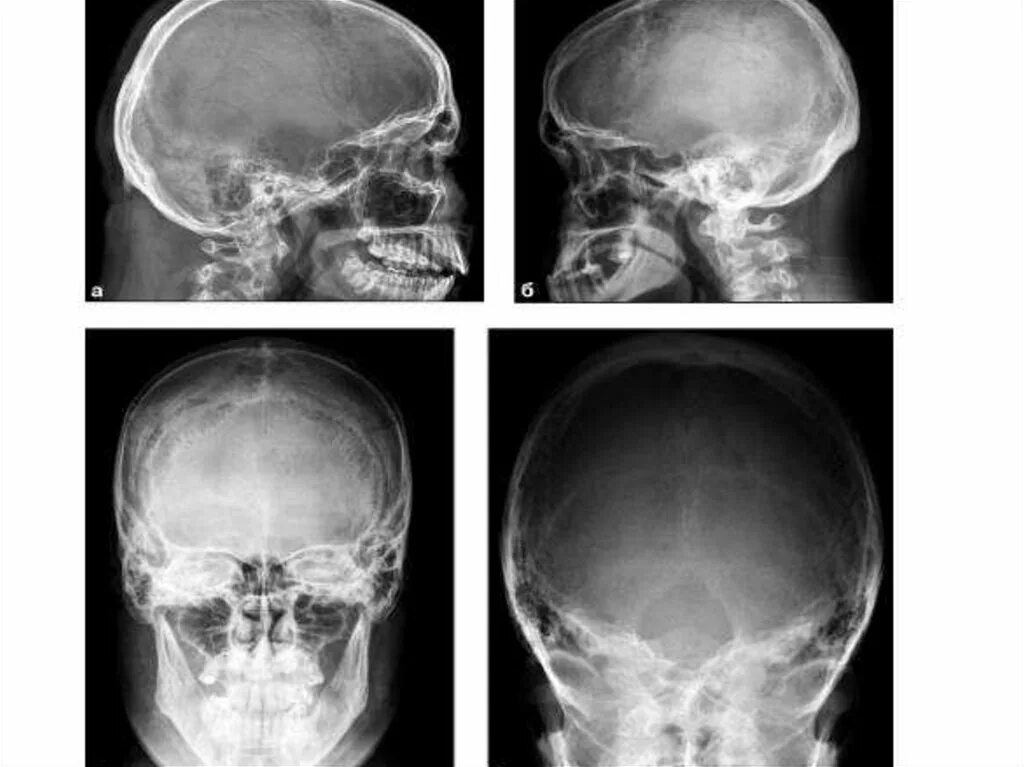

Череп проекции